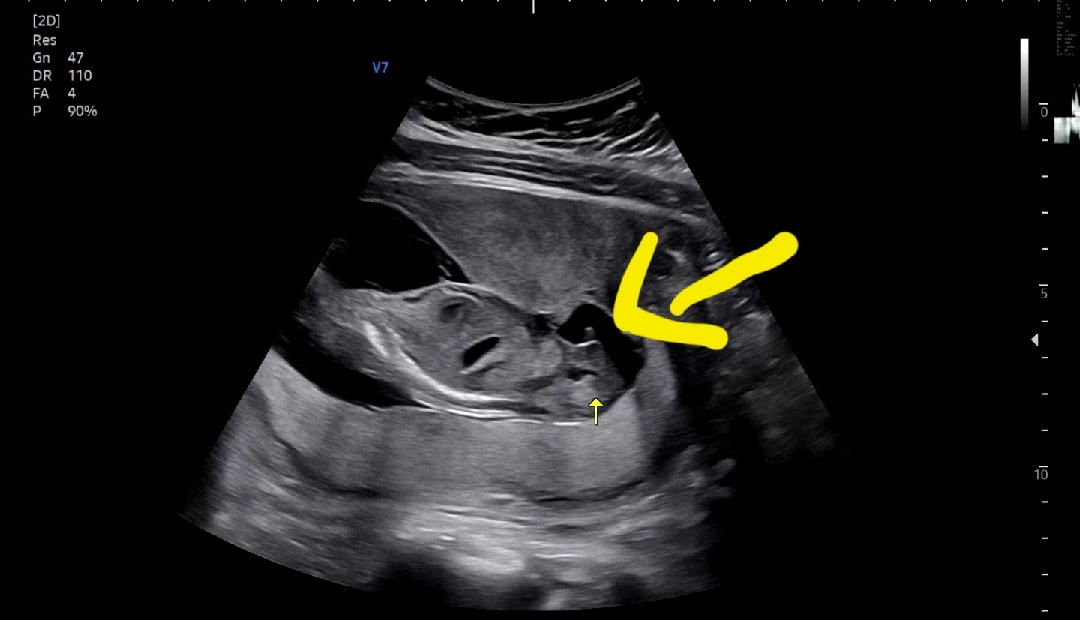

아들맘 확정 건강하게 잘 자라줘서 고마워♡

걱정반 기대반 한달 기다림이 넘 길었네요. 친정엄마가 처음부터 아들 같다고 확신 하셨는데 정말 아들이었어요. 시어머니는 딸 원하셨는데 아쉬워 하시네요 ㅎㅎ 초음파 보는내 의사선생님 대충 말하고 넘어갔는데 아들인건 확실하게 얘기해 주시더라구요. 임신기간 입덧도 없고 별다른 증상 없이 무탈히 지나가는게 효자인게 확실합니다 ㅎㅎ 실제 초음파 볼땐 존재감 뚜렷했는데 녹화는 짧게 지나가더라구요. 겨우 캡쳐 했네요. 성별 상관없이 건강하게만 자라기를 매일 기도 하고 있었어요. 남은 기간동안 지금처럼 잘 자라서 만나자 우리효자!!